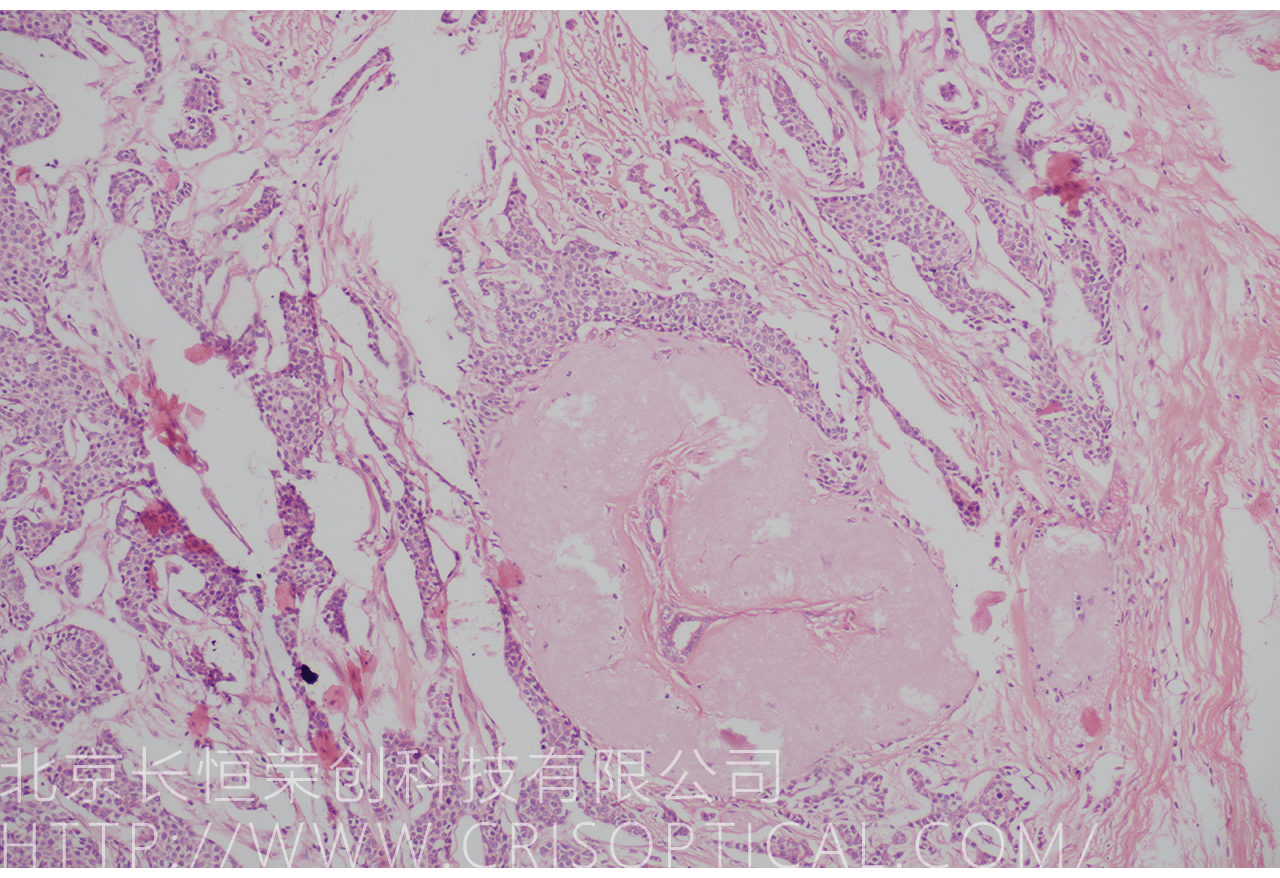

病理切片觀察是一種重要的醫(yī)學(xué)實(shí)踐,通過對(duì)組織和細(xì)胞切片的

顯微鏡觀察,幫助醫(yī)生診斷疾病、評(píng)估病情和制定治療方案。病理切片觀察在

臨床醫(yī)學(xué)、癌癥診斷、外科手術(shù)和疾病研究中發(fā)揮著關(guān)鍵作用。

腫瘤診斷:對(duì)癌癥和其他腫瘤的病理切片觀察是確定腫瘤類型、分級(jí)和分期的關(guān)鍵步驟。醫(yī)生通過觀察組織樣本中的細(xì)胞形態(tài)、核形狀、分裂活性和其他特征,可以識(shí)別腫瘤的類型,幫助決定治療方法。